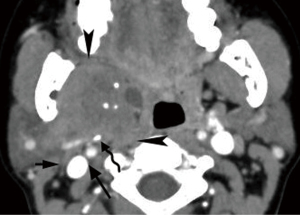

Paraganglion is extra-adrenal neuroendocrine tissue, capable of producing and storing vasoactive and neurotransmitter substances, distributed in the whole body (22). Paraganglia in the head and neck migrate along a branchiomeric distribution (23). Paragangliomas, the tumors of the paraganglia, arise from this specialized tissue at any site along these specific locations in the head and neck with the four most common sites being the CCA bifurcation, the jugular foramen, along the vagus nerve, and within the middle ear.

Paragangliomas have characteristic CT and MRI appearances based on their hypervascularity. They are usually homogeneously or heterogeneously hyperdense or hyperintense after contrast enhancement, with incorporation of adjacent arteries on CT and MRI (Figures 10-12) (12). On MRI, serpentine and punctate areas of signal void representing high vascular flow are interspersed with areas of high signal intensity caused by slowly flowing blood. This “salt-and-pepper” pattern is seen in all lesions greater than 2 cm in maximal dimension (Figure 11) (23-25). Carotid body tumors (paragangliomas of the carotid body) splay the ICA and the external carotid artery (ECA) and may encase the ICA and ECA (Figure 10), whereas vagal paragangliomas displace both ICA and ECA anteromedially, separating these vessels from the IJV (Figure 11). Paragangliomas may be multicentric and can manifest as unilateral or bilateral lesions, either simultaneously or sequentially. Only a very low percentage of 3% of paragangliomas will undergo malignant transformation (25). The presence of local lymph node involvement, distant metastases, or extensive local invasion will establish the malignancy of a paraganglioma.